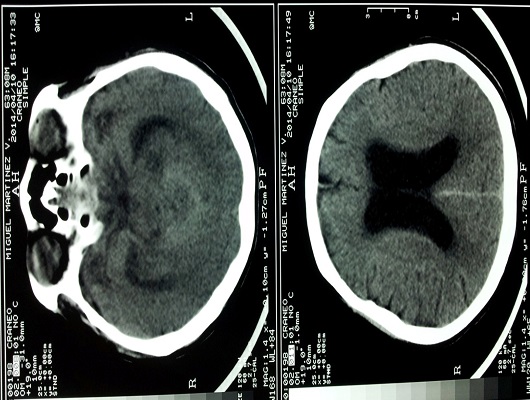

Descripción tomografica: Tc simple y contrastada, lesión de fosa posterior de predominio vermiano, que obstruye 4to. Ventriculo produciendo hidrocefalea supratentorial. Evolucionó a más deterioro, mirada congelada, llegando al coma, en los 5 días despues falleció. No se aceptó derivación ventriculoperitoneal con toma de muestra de LCR, propuesta por neurocirugía.